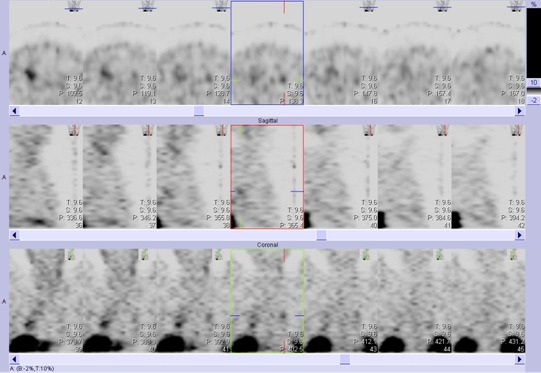

/Obr.č.2: Tomografická scintigrafie hrudníku 5 hod. po aplikaci OctreoScanu /

/Obr.č.4: Tomografická scintigrafie hrudníku 24 hod. po aplikaci OctreoScanu /